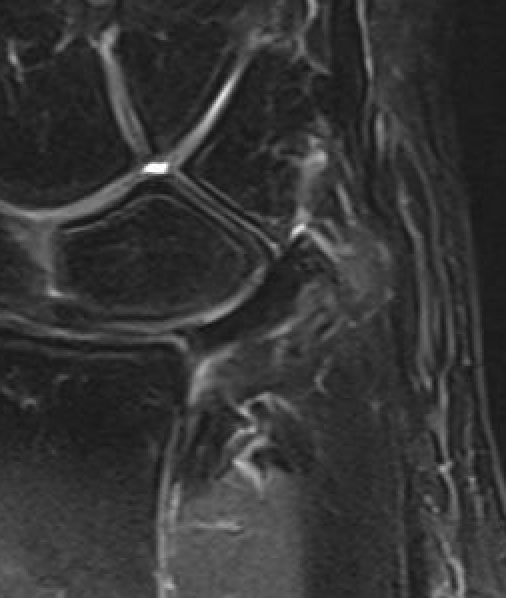

Ulna sided tear

Ulna sided TFCC tears

Technique arthroscopic repair

Ulna / foveal sided TFCC tear on arthroscopy